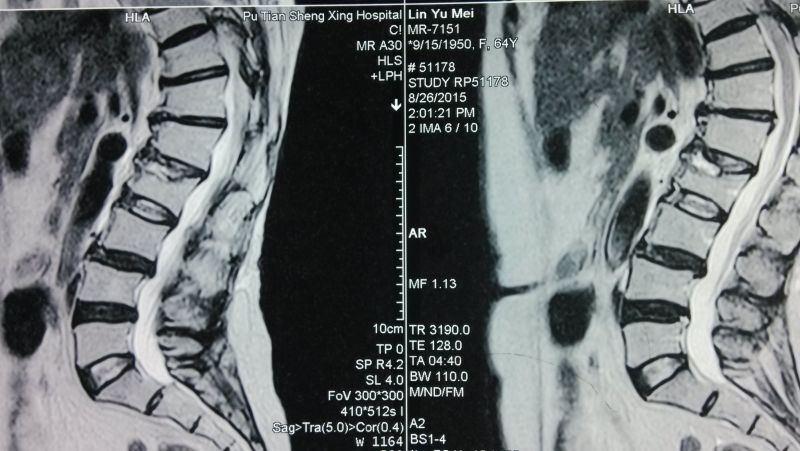

術(shù)前MRI (2)